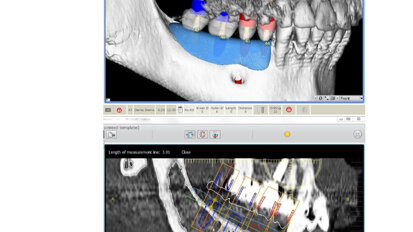

Nový úsměv za jeden den

Čt. 28. května 2020